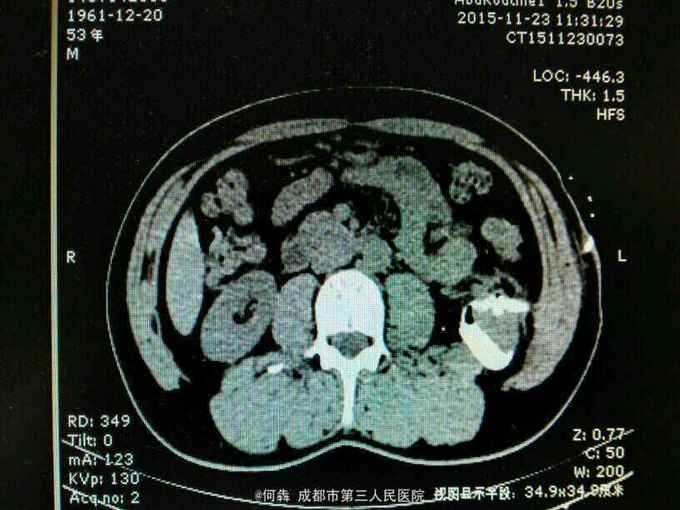

53岁,男性,因“腹腔镜下双肾囊肿切除术后1年余,左腰部窦道形成10月余”入院。无高血压病及糖尿病。

左腰部窦道形成伴少许脓液。窦道脓液培养出绿脓杆菌。

腹腔镜双肾囊肿切除术后窦道形成伴感染。现使用敏感抗生素派拉西林舒巴坦抗感染。